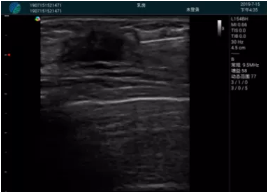

腺體內(nèi)部清晰顯示一低回聲塊影,形態(tài)不規(guī)則,邊界模糊,邊緣呈毛刺狀,內(nèi)部見砂礫樣鈣化

M20引導(dǎo)下穿刺活檢術(shù)